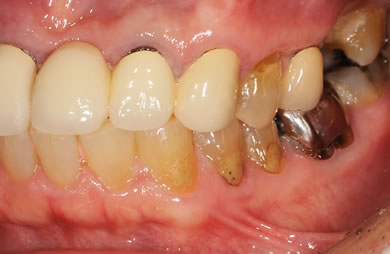

主訴 前の差し歯がぐらつくようになり、差し歯の根元が割れているような感覚がある。治療内容を相談したく来院。

治療方針 ソケットリフト法に再生療法を併用しつつ、スピードインプラントにより治療期間を軽減し、機能的・審美的回復を行う。

治療内容 インプラント4本(抜歯即日スピードインプラント+ソケットリフト)、メタルボンドセラミック6本、ハイブリッドセラミック1本、テンポラリーインプラント2本